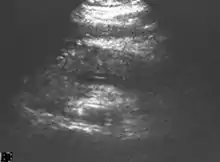

Abdominal ultrasonography of acute pancreatitis

On abdominal ultrasonography, the finding of a hypoechoic and bulky pancreas is regarded as diagnostic of acute pancreatitis.